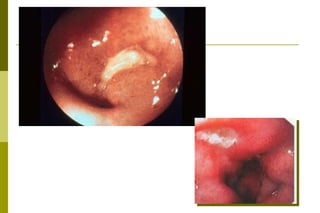

Úlcera pépticaMacroscopia: em gerallesão é única. Lesão arredondada ou ovalada, com diâmetro em torno de 0,5 ou 2,0 cm.As bordas são regulares, pouco elevadas e cortadas a pique, tendendo a se afunilar à medida que se aprofundam na parede do órgão. O fundo pode ser limpo ou recoberto por material necrótico brancacento, tecido de granulação avermelhado ou por tecido fibroso.

Úlcera péptica:  ClassificaçãoSuperficial -até a submucosa. Profunda -até a muscular própria ou até a serosa. Perfurante -ultrapassa todas as camadas da parede e se abre na cavidade peritoneal. Penetrante -ultrapassa todas as camadas, mas fica tamponada por órgãos vizinhos. Calosa - caracterizada pela proliferação exuberante de tecido conjuntivo fibroso nas bordas e no fundo da úlcera. A neoformação conjuntiva protege contra a perfuração mas, pode provocar deformação ou estenose do órgão ou semi obstrução da luz.

Úlcera péptica:  microscopia Úlcera péptica ativa: camada de tecido necrótico (fibrinóide), presente no fundo da lesão; camada de exsudato celular (predomínio de neutrófilos);  camada  de tecido de granulação;  camada de tecido fibroso cicatricial. Úlcera péptica inativa:necrose escassa,exudatode neutrófilos é discreto.em alguns indivíduos grande camada fibrosa pode ser observada.

Úlcera péptica: conseqüências e complicações:A hemorragia é a mais comum (discretas ou maciça com hematêmase ou melena). Pode ocorrer perfuração com formação de aderências (pela peritonite). Estenoses e/ou deformações do órgãoCancerização?.

Úlcera pépticaMacroscopia: emgerallesão é única. Lesão arredondada ou ovalada, com diâmetro em torno de 0,5 ou 2,0 cm.As bordas são regulares, pouco elevadas e cortadas a pique, tendendo a se afunilar à medida que se aprofundam na parede do órgão. O fundo pode ser limpo ou recoberto por material necrótico brancacento, tecido de granulação avermelhado ou por tecido fibroso.

Úlcera péptica: conseqüênciase complicações:A hemorragia é a mais comum (discretas ou maciça com hematêmase ou melena). Pode ocorrer perfuração com formação de aderências (pela peritonite). Estenoses e/ou deformações do órgãoCancerização?.